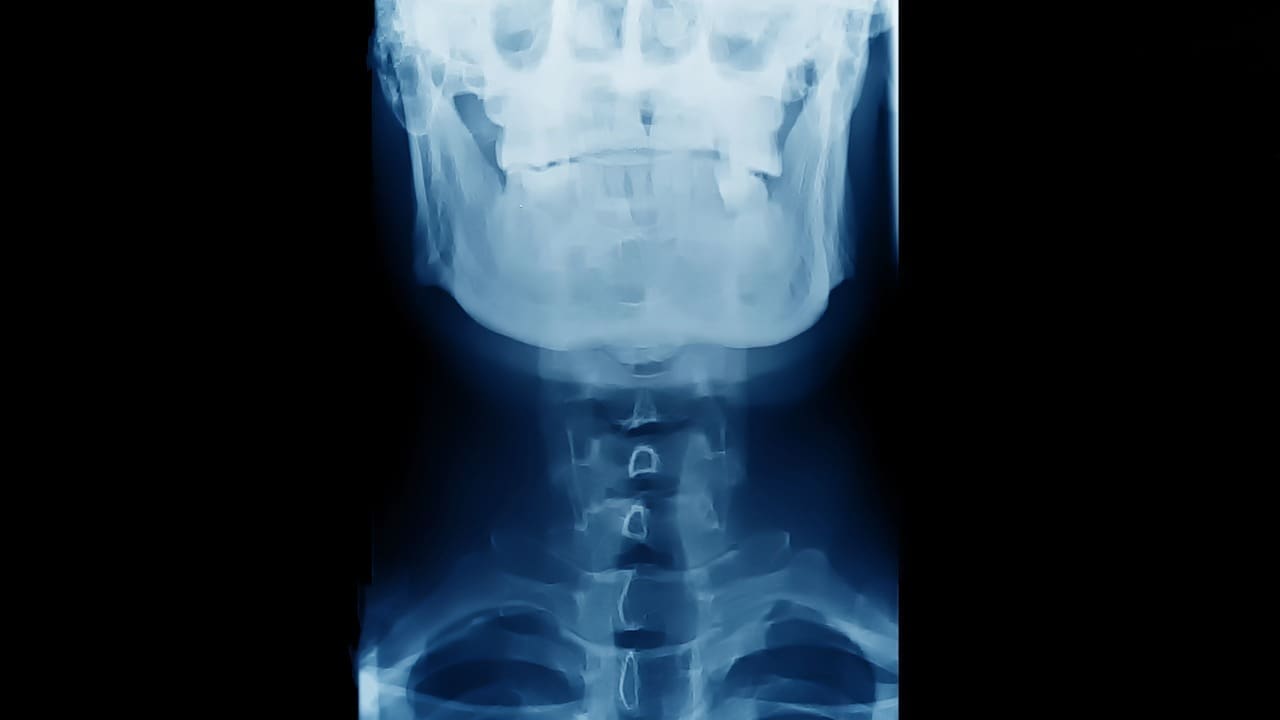

Diagnostic Considerations: Lesions on the Spine

Modern Diagnostic Techniques

Modern tools like MRI, CT scans, and biopsy are essential for diagnosing spinal lesions. They help doctors see the lesion, understand its nature, and choose the best treatment.